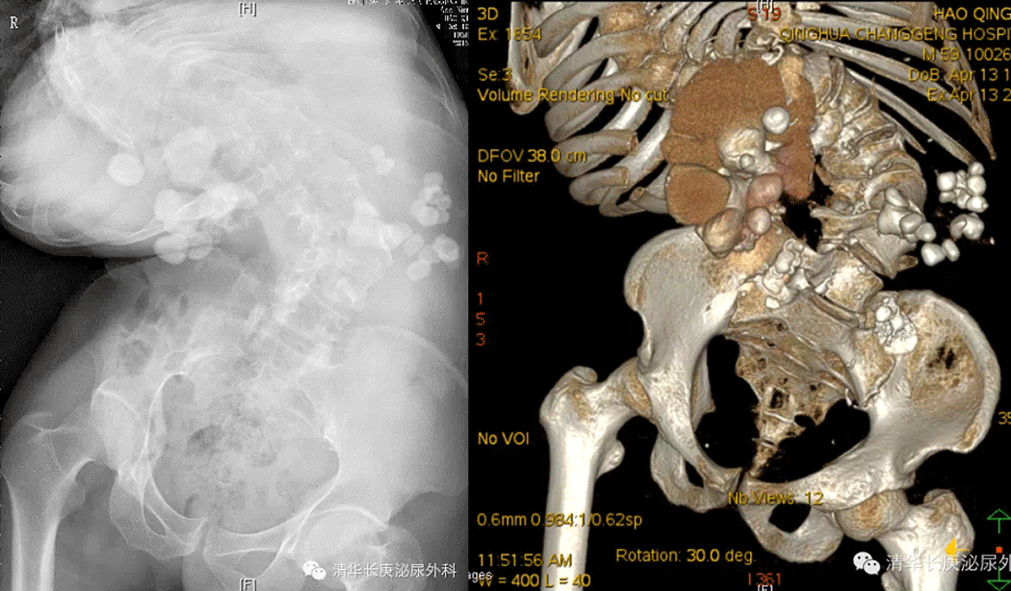

次日的手术演示为学员们献上一场结石微创治疗的饕餮盛宴,本期手术病例共展示了8例复杂上尿路结石的微创治疗手术,包括双侧完全鹿角形结石二期PCNL、小儿肾输尿管软镜(3岁)及小儿PCNL(6个月),脊柱畸形合并复杂肾结石PCNL,马蹄肾合并肾结石PCNL等,8例手术均取得了圆满成功。值得一提的是小儿PCNL为出生6个月的早产儿,体重仅7.5kg,刷新了清华长庚医院麻醉及手术的最小年龄,反映了李建兴主任高超的术前研判和精湛的手术技艺。